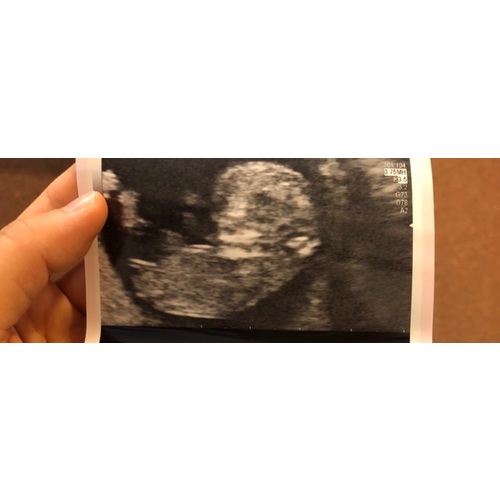

Ik denk een jongentje

Lieve mensen, elke baby is in het begin een meisje vanuit daar groeit de clitoris naar een piemeltje, of het blijft. Echt wachten tot zeker 16 weken....